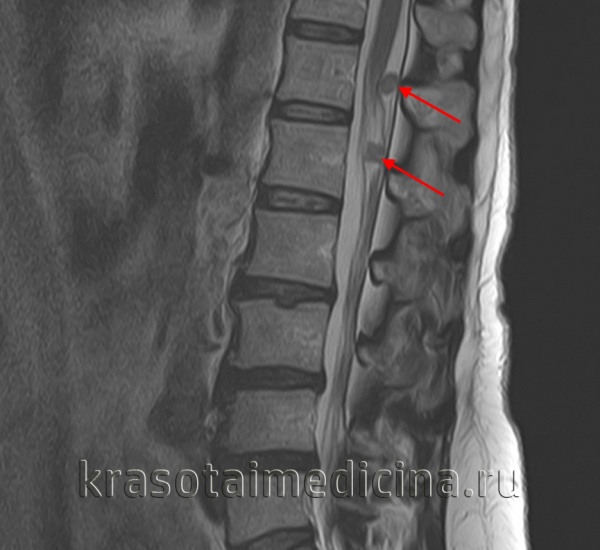

- Рентгенография позвоночника. Наиболее доступным методом определения экстравазального сдавления вертебральной артерии считают рентгенографию позвоночника с функциональными пробами. Снимки выполняют в прямой и боковой проекциях при максимальном сгибании или разгибании шейного отдела.

- Томографические методы. МРТ выявляет даже мельчайшие ишемические очаги, расположенные в любых отделах ЦНС, поэтому является наиболее информативным методом нейровизуализации. Режим ангиографии, особенно в комбинации с УЗДГ, позволяет комплексно оценить состояние магистральных артерий. Важные данные о вертеброгенной природе болезни предоставляют КТ и МРТ шейного отдела позвоночника.